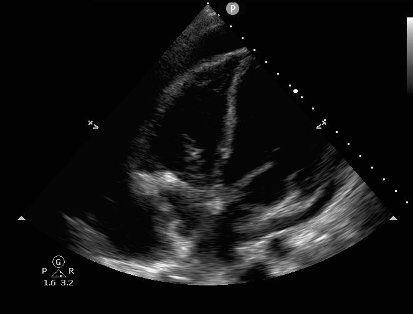

There are two methods to establish systolic/diastolic collapse. First, one can record a video clip in either the apical four-chamber view or subxiphoid view and rewind slowly to look at the chambers when the mitral valve is open (diastole) or closed (systole). Second, one can place the M mode marker over the anterior leaflet of the mitral valve to produce the image below (Figure 2). The mitral valve tracing produces an E and A wave during mitral opening, and thus ventricular diastole. Ventricular wall collapse during this peak establishes tamponade.5-8

Like clinical signs of tamponade, echocardiographic signs aren’t perfect. Anything that increases cardiac chamber pressures at baseline, such as pulmonary hypertension, pulmonary embolism, and left to right cardiac shunts, will make RA and RV collapse later findings. Conditions, such as volume depletion, that decrease right intraventricular pressures would do the opposite. Because of this, cardiac chambers may briefly collapse in diastole without tamponade. RA collapse for more than one-third of the cardiac cycle is therefore more specific than transient collapse.9

Figure 2: M Mode tracing of mitral valve demonstrating diastolic right ventricular collapse. Image courtesy of Dr. Sarah Murthi.